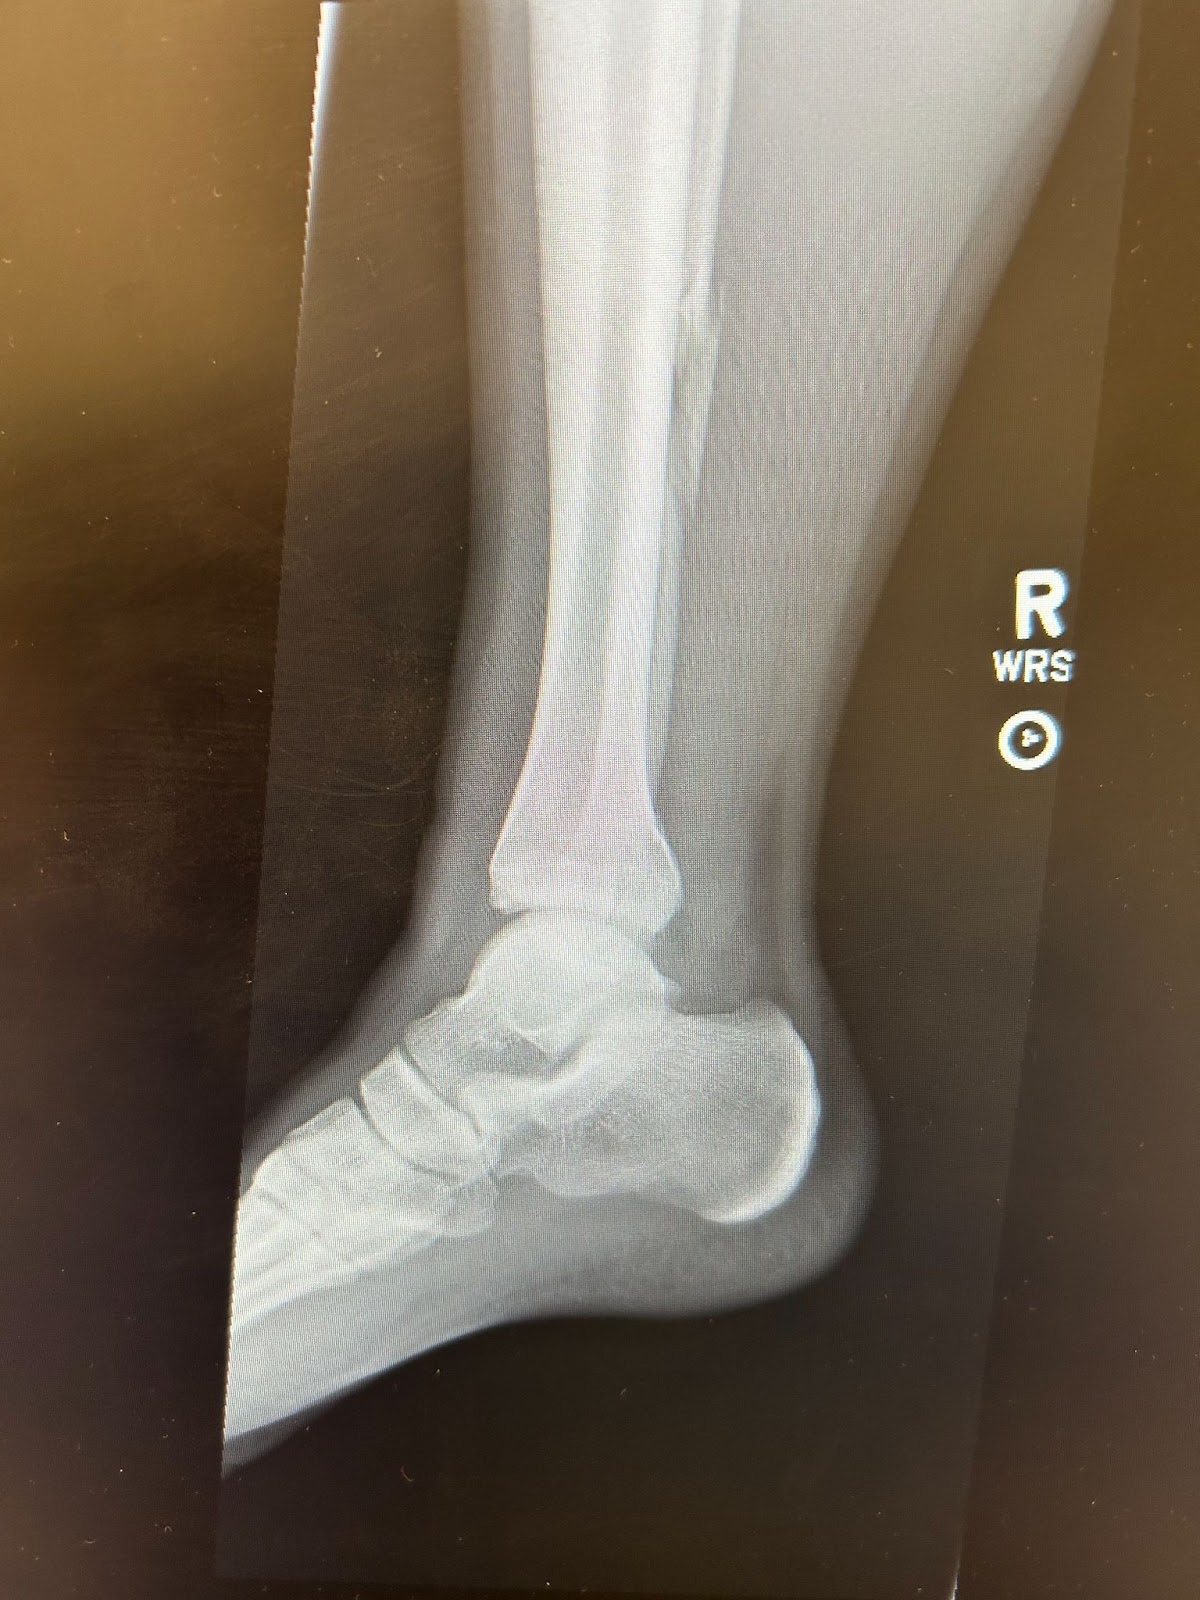

A 26 year old male year presents with right ankle pain after jumping out of a truck at work. There is significant effusion and generalized lower leg pain but no obvious deformity.

Image 1. AP x-ray. Courtesy of Ortho EM Pearls Image Bank